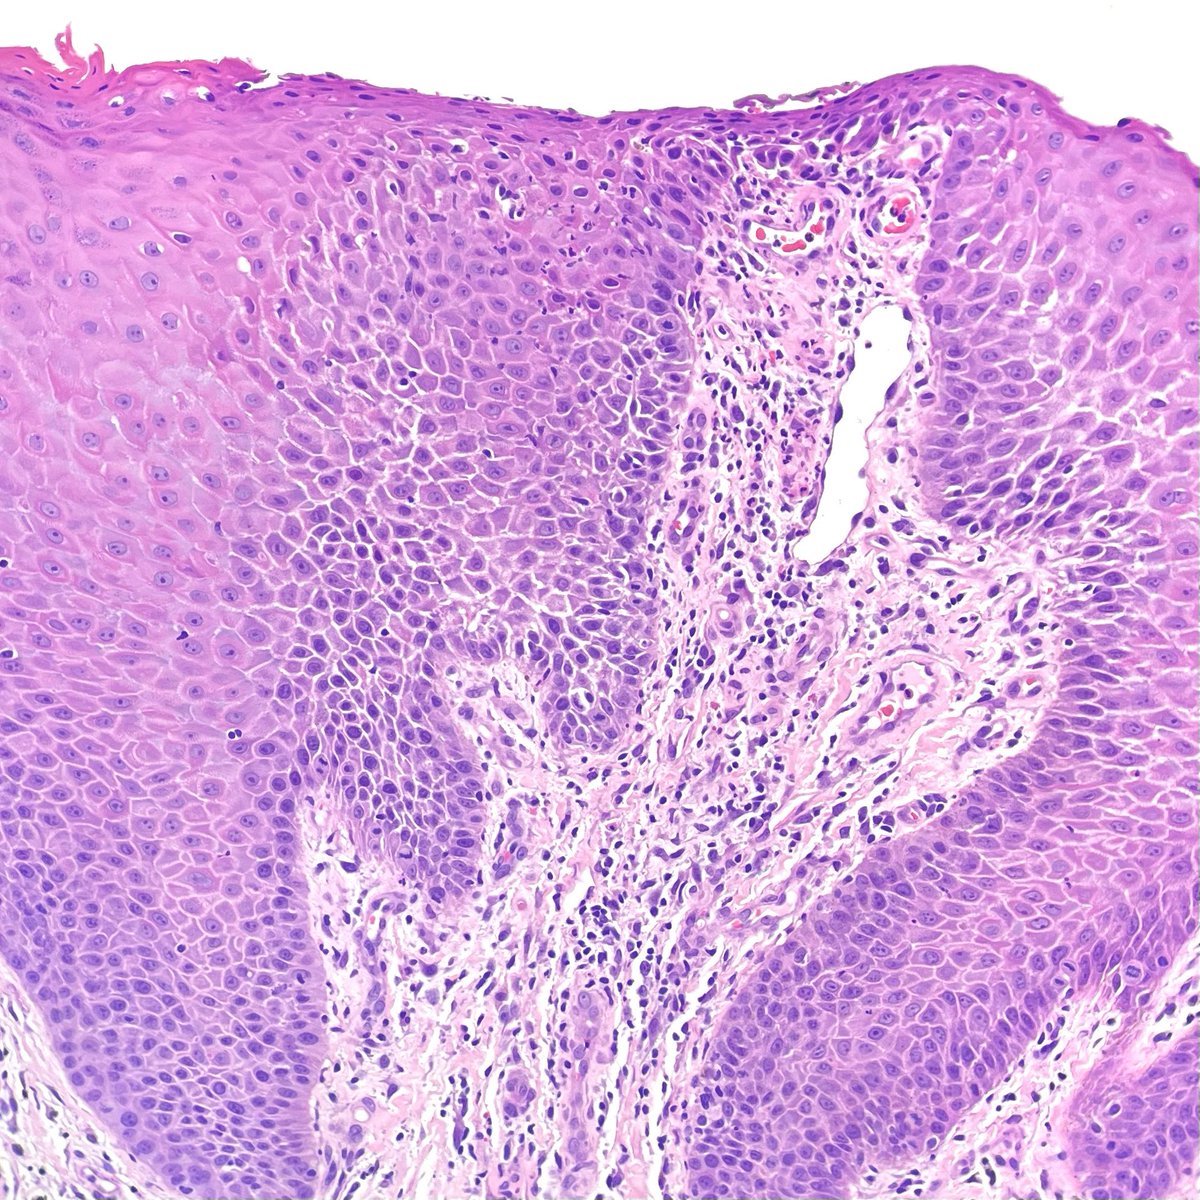

Any thoughts on this beautiful, elegant creature that "crawled" into the colonic mucosa and presented as polyp !! I have been googling it for ages and can't find a morphologic fit with any of the adult/ larval parasitic forms that I have ever encountered. Pt is asymptomatic.